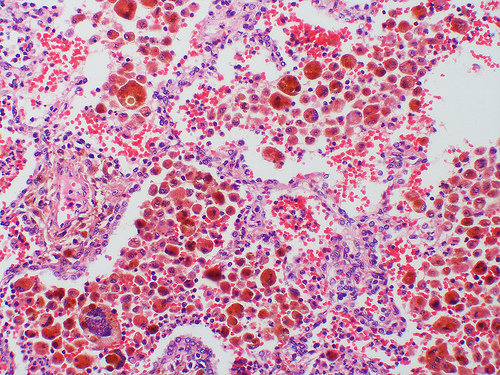

Udoskonalone czerwone krwinki

Respirocyty mają 1 mikrometr, czyli są osiem razy mniejsze niż erytrocyty. Są jednak stworzone tak, by magazynować i transportować ok. 236 razy więcej tlenu i dwutlenku węgla. Bezpieczeństwo takiego transportu zapewnia grafen – nowoczesny materiał, dzięki któremu komórki byłyby bardzo wytrzymałe i elastyczne. Respirocyty skierowane w odpowiednie miejsce organizmu natychmiast uwalniają tlen do krwi.